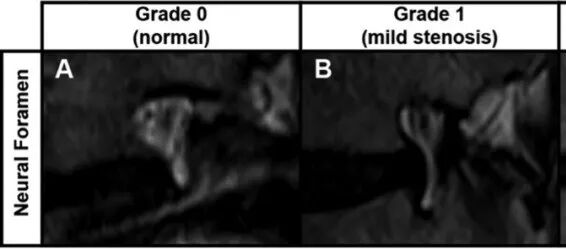

![]()

椎间孔(NF)狭窄等级实例:(A) 0 级(正常)NF 狭窄,神经周围脂肪没有消失。(B) 1 级(轻度)NF 狭窄,伴头尾方向神经周围脂肪消失(前后方向神经周围脂肪消失也符合该等级)。(C) 2 级(中度)NF 狭窄,神经周围脂肪在各个方向几乎完全消失,但神经根没有形态学变化。(D) 3 级(严重)NF 狭窄伴神经根受压和形态学改变。